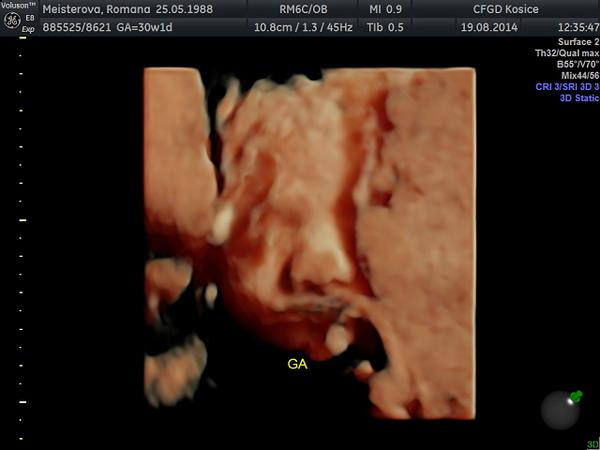

@5romanna5 a to morfo sono sa robi aj okolo toho 30tt, ze? chcela by som nan ist niekde, kde sa budu dat drobcekovia pozriet aj tym 3D, lebo muzik na samotne 3D odmieta ist, ze naco. nam ich na poradni meria teraz uz podla hlaviciek, bruska a stehennej kosti, ale nepovedal nam nic